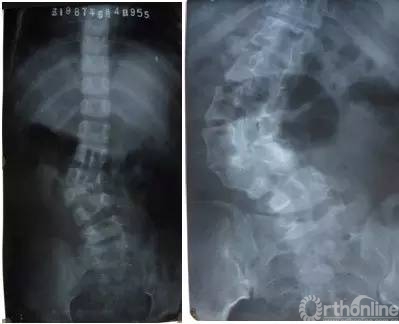

5岁患儿,腰椎半椎体畸形,发现时畸形轻微,未予治疗;19岁时发展成严重的脊柱侧凸,导致严重“罗锅”外观并导致严重的腰背疼痛,需手术矫正畸形,由于畸形严重、僵硬,手术难度、风险增大,且需融合全部腰椎,术后患者弯腰会受明显影响。

3岁患儿,腰椎完全分节半椎体,行半椎体切除短节段融合术,术后4年随访提示矫形维持良好,在获得“直”的脊柱的同时保留了腰椎活动节段,患者弯腰等活动受影响很小。